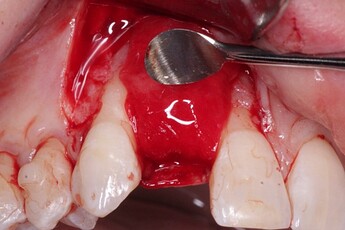

Pic 2

osseoseal-2

An implant was placed in site #7 with an existing buccal bone defect (Pictures 1 & 2). Prior to placing the bone graft over the implant, the membrane is measured and trimmed and tucked under the palatal flap trying to avoid wetting the entire membrane (Picture 3). The particulate bone graft (DALI Classic Cortical Cancellous Mix) is placed over the implant surface to restore the defect (Picture 4). The membrane is folded over the crest and onto and slightly beyond the particulate bone graft while slowly dropping saline onto the membrane (Picture 5). This enables the membrane to contour and drape over the graft and “seal” the graft off from the surrounding soft tissue (Picture 6 and 7). Sutures are then used to achieve primary closure over the GBR site (Picture 8).